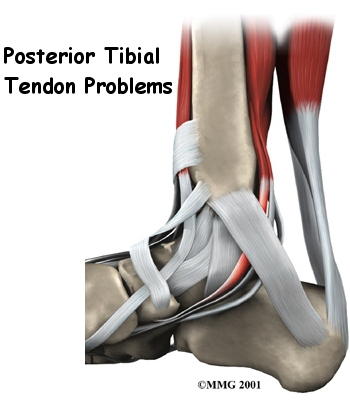

Posterior Tibial Tendonitis

Posterior tibial tendonitis, which is also called tendon dysfunction, is a common problem that affects the ankle and foot. It develops due to inflammation of the posterior tibial tendon. If the tendon tears, it loses the ability to properly stabilize the arch of the foot and can lead to painful flatfoot. This issue is usually caused by age-related degeneration.

Related Document: Ari Levine PT, PC's Guide to Posterior Tibial Tendon Problems